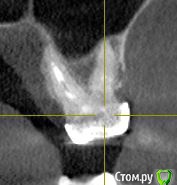

ТСВ Опубликовано 29 июня, 2015 Поделиться Опубликовано 29 июня, 2015 Подскажите пожалуйста!17 зуб, на нем мост. Сделал КТ, там такая картина, прикрепляю несколько срезов.Если это киста, то только удаление вместе с зубом? Ссылка на комментарий

red_butler Опубликовано 29 июня, 2015 Поделиться Опубликовано 29 июня, 2015 Кисты нет, а вот повторное лечение корневых каналов требуется 2 Ссылка на комментарий

Alejandro Опубликовано 30 июня, 2015 Поделиться Опубликовано 30 июня, 2015 Вы имеете в виду очаг просветления в области середины дистального щёчного корня? Ссылка на комментарий